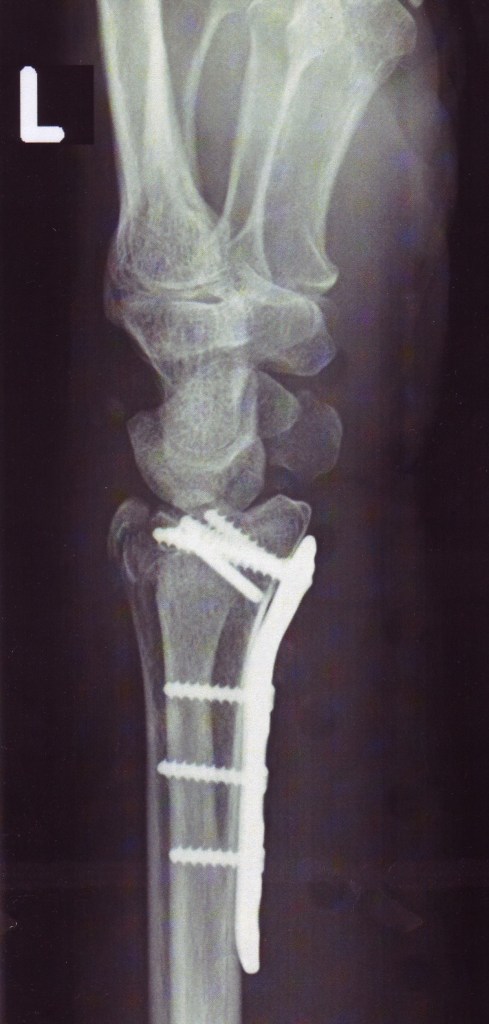

Stimmt 2016 habe ich mir den Arm zertrümmert und konnte keine Fotos machen, weil ich keine Kamera halten konnte.

Nachher unverhofft auf Oland und da konnte ich schon nix anfassen.

Tatsächlich hat mir der Armbruch eine dringend benötigte Auszeit von der Mutterpflege beschert, bis hin zu dem Drama kurz vor Weihnachten.